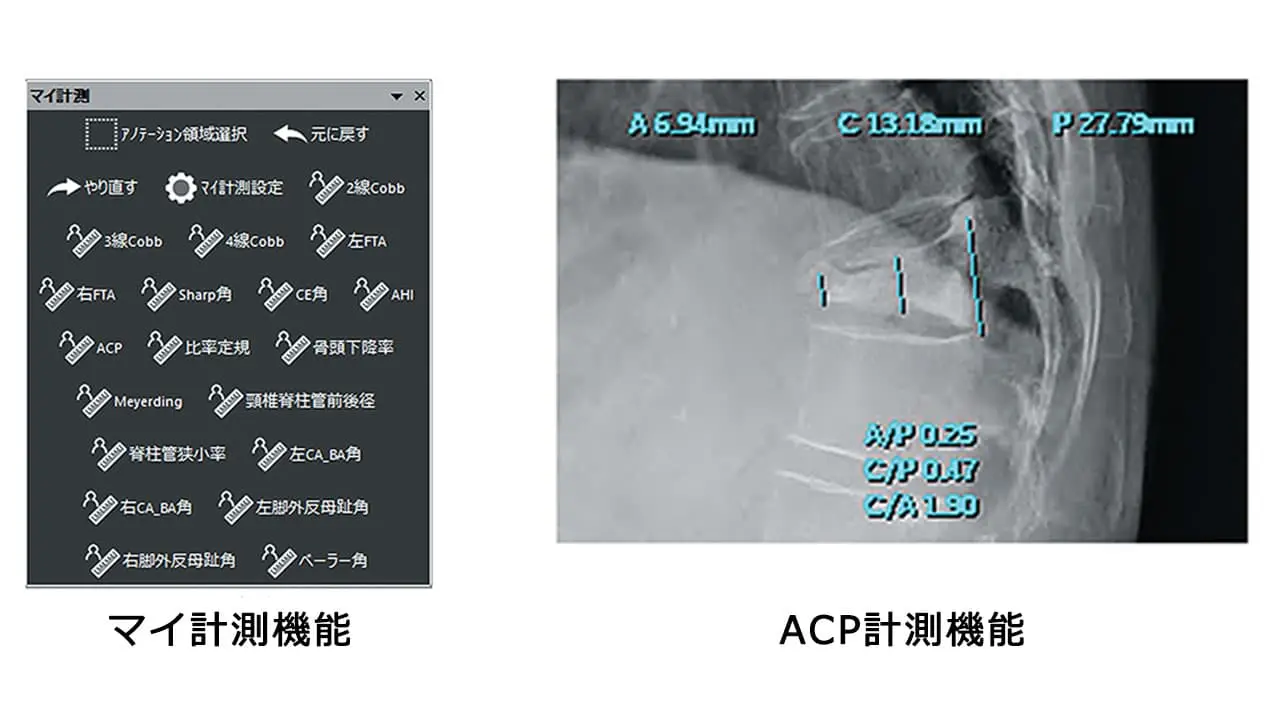

・コブ角やCE角、シャープ角等の整形用計測機能に対応

計測カスタマイズ機能

距離や⾓度計測などの⼀般的な計測はもちろん、少し複雑な計測機能を登録できる“マイ計測機能”を標準搭載。